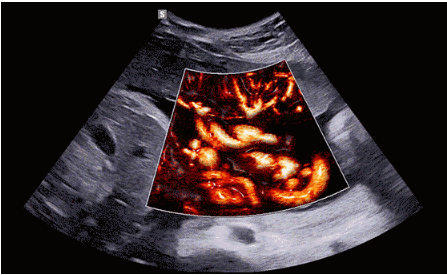

CrystalLive?是三星最新的超聲成像引擎,同時增強了2D圖像處理能力、3D渲染能力和彩色信號處理能力,能夠在復雜情況下提供出色的圖像性能,具備檢測外周血管、微循環(huán)血流的能力。